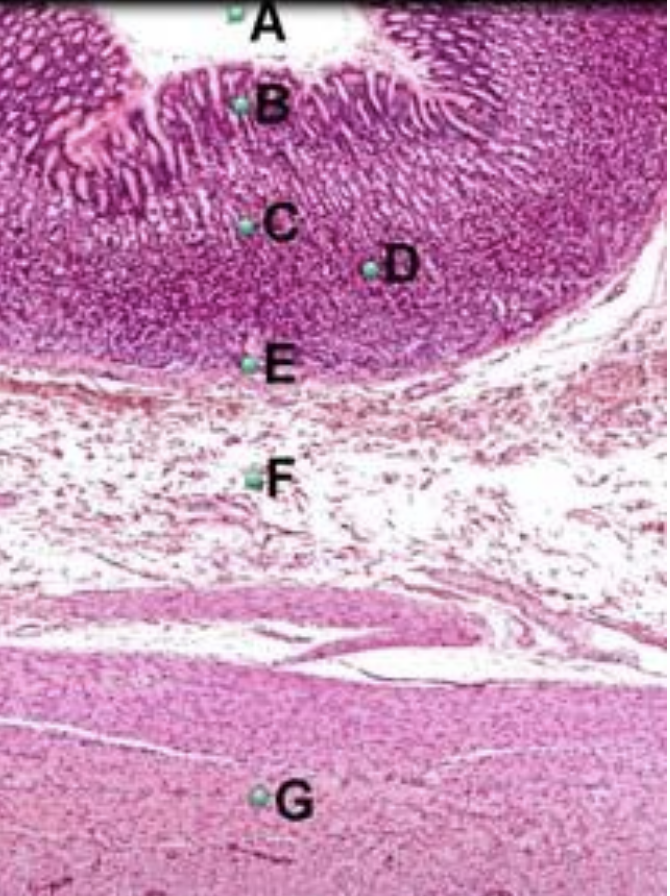

Part A?

mucosa of esophagus

Part B?

epithelium of esophagus

Part C?

muscularis mucosae of esophagus

Part D?

submucosa of esophagus

Part E?

muscularis externa of esophagus

Part F?

adventitia of esophagus